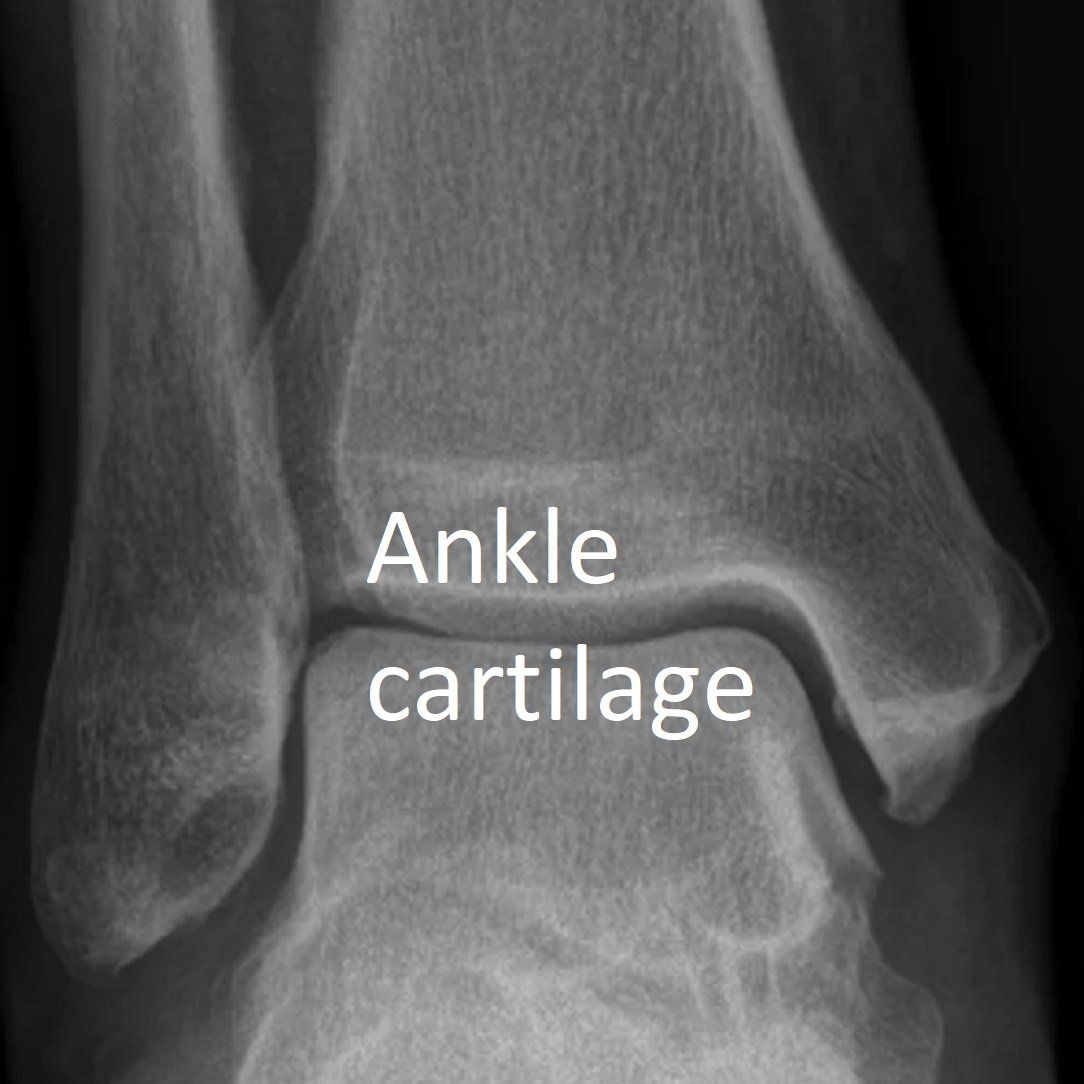

The ankle joint surfaces are covered by a smooth white layer of cartilage. This thin but very resilient tissue helps cushion the ankle and allows it to move smoothly. It is the "gap" seen between bone on X-rays.

See X-ray and arthroscopic images below.

- weight-bearing X-rays of the ankle